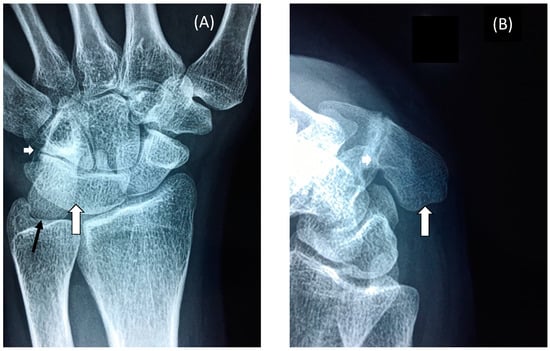

3.2. Restricted Wrist Rotation Associated with Evolutionary Retrograde Wrist Morphology

- Pisiform and its elongation (retrogression) and extension into the radio-ulnar joint that restricted wrist rotation.